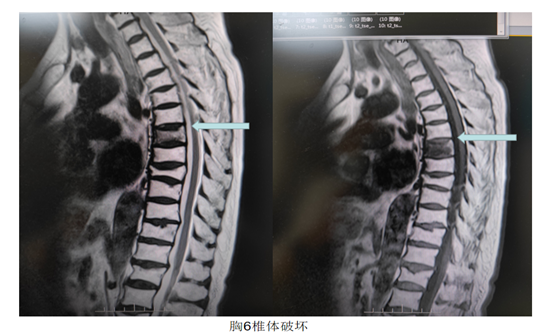

黃奶奶是一位肝癌術(shù)后復(fù)發(fā)患者,近1個(gè)多月來(lái)出現(xiàn)背部的疼痛不適,日漸加重,活動(dòng)時(shí)疼痛癥狀加劇,后發(fā)展至無(wú)法起床,生活不能自理。黃奶奶在門(mén)診口服止疼藥物后,癥狀改善不明顯,聽(tīng)他人介紹來(lái)到腫瘤介入科門(mén)診就診。經(jīng)全脊柱磁共振檢查,發(fā)現(xiàn)黃奶奶胸6椎體明顯水腫并伴有骨質(zhì)破壞,結(jié)合病史考慮系肝癌胸6椎體轉(zhuǎn)移。經(jīng)過(guò)科室團(tuán)隊(duì)的病情討論,考慮為其進(jìn)行DSA下經(jīng)皮胸6椎體成形術(shù)。經(jīng)過(guò)與患者家屬的充分溝通和術(shù)前精心的準(zhǔn)備,5月28日,科室團(tuán)隊(duì)為其順利實(shí)施手術(shù),手術(shù)時(shí)間僅20分鐘,手術(shù)結(jié)束后黃奶奶背部疼痛立刻得到了緩解。黃奶奶返回病房臥床兩小時(shí)后,即可下床自由活動(dòng),手術(shù)第二日黃奶奶出院。